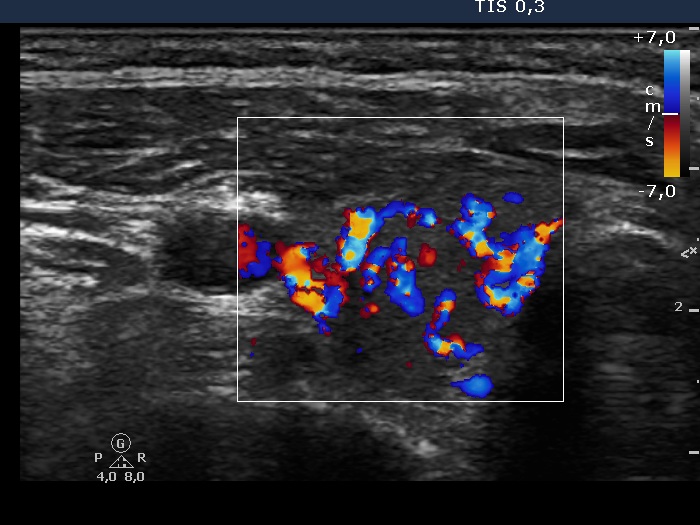

Ultrasonography. The thyroid was composed of circumscribed echonormal and minimally hypoechogenic areas divided by fibrous tissue. None of these areas corresponded to a nodule in a pathological sense.